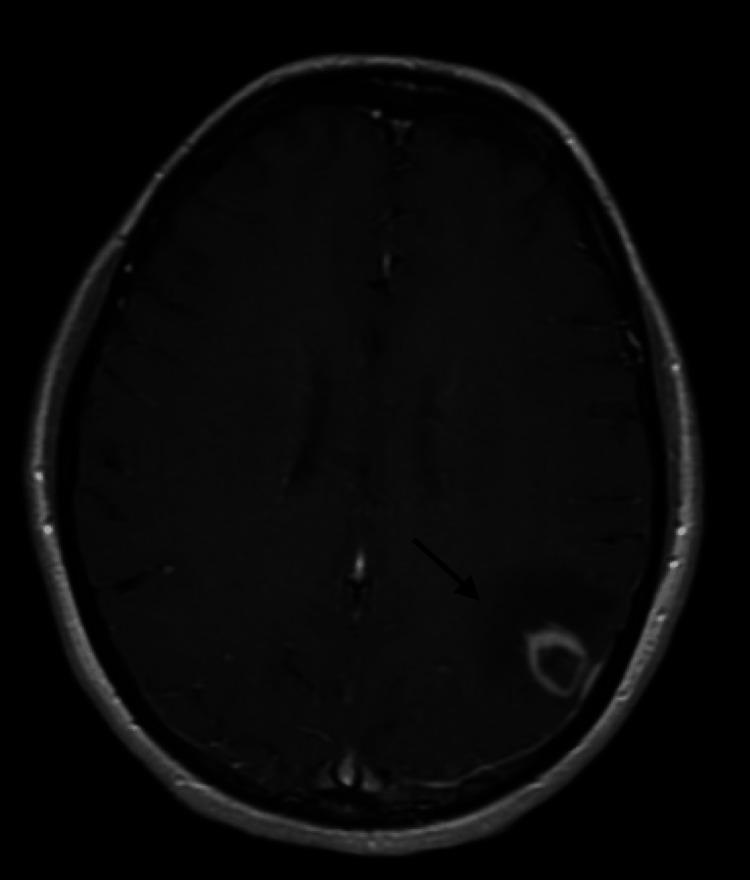

Post-transplant lymphoproliferative disease (PTLD) is a complication of solid organ and hematopoietic stem cell transplantation that occurs as a result of immunosuppression. PTLD isolated to the central nervous system (CNS) is a rare disease and it presents with nonspecific signs and symptoms. Optimal therapy guidelines have not yet been established for CNS PTLD. Here, we report a case of successful treatment of CNS PTLD in an adult female following two subsequent kidney transplants. Initial management was with immunosuppression reduction and a trial of rituximab. There were concerns regarding using methotrexate (MTX) given the patient's fragile transplant status. Magnetic resonance imaging of the brain following four cycles of rituximab revealed the progression of the disease. Subsequently, high-dose MTX (HD-MTX) was considered within the constraints of potential kidney toxicities given her transplant status and chronic kidney disease. Potential toxicities from other therapies, such as brain radiation, also factored into the final decision. The patient was treated with one cycle of a combination of rituximab and HD-MTX 1 g/m. The patient tolerated HD-MTX and did not have evidence of renal toxicity in laboratory studies. Following that, she was started on a reduced dose of HD-MTX at 2 g/m every two weeks instead of the higher MTX dose range of 3.5 to 8 g/m, which was a shared decision with the patient and nephrology after weighing the risk of kidney dysfunction with the possibility of a less than optimal response with regards to her lymphoma. She was followed with a magnetic resonance imaging of the brain, which demonstrated a complete response after four cycles. Further consolidation treatments with HD-MTX 2 g/m every four weeks were administered to complete one year of treatment. Following the completion of chemotherapy, the patient was able to achieve and maintain a complete response without affecting her kidney function. She continues to do well one year following treatment. This case highlights the significance of tailoring therapy to each individual based on their comorbidities and clinical response, as well as the possible merit in exploring the use of a reduced dose of HD-MTX in the treatment of CNS PTLD in patients at high risk for renal toxicity.

移植后淋巴细胞增生性疾病(PTLD)是实体器官和造血干细胞移植的一种并发症,由免疫抑制引起。孤立于中枢神经系统(CNS)的PTLD是一种罕见疾病,表现为非特异性体征和症状。目前尚未建立针对CNS PTLD的最佳治疗指南。在此,我们报告一例成年女性在接受两次肾移植后成功治疗CNS PTLD的病例。初始治疗是减少免疫抑制并试用利妥昔单抗。考虑到患者脆弱的移植状态,对使用甲氨蝶呤(MTX)存在担忧。利妥昔单抗四个周期治疗后进行的脑部磁共振成像显示疾病进展。随后,鉴于她的移植状态和慢性肾脏病,在考虑潜在肾脏毒性的情况下,考虑使用大剂量MTX(HD-MTX)。其他治疗方法(如脑部放疗)的潜在毒性也在最终决策中予以考虑。患者接受了一个周期的利妥昔单抗与1 g/m的HD-MTX联合治疗。患者耐受HD-MTX,实验室检查未发现肾毒性证据。此后,她开始每两周接受一次剂量降低至2 g/m的HD-MTX治疗,而非更高的3.5至8 g/m的MTX剂量范围,这是在与患者及肾脏病学专家权衡肾功能障碍风险与淋巴瘤反应欠佳可能性后共同做出的决定。对她进行脑部磁共振成像随访,结果显示四个周期后完全缓解。之后每四周给予2 g/m的HD-MTX进行进一步巩固治疗,以完成一年的治疗。化疗完成后,患者能够实现并维持完全缓解,且未影响其肾功能。治疗一年后她情况仍然良好。该病例强调了根据患者合并症和临床反应制定个体化治疗方案的重要性,以及在肾毒性高危患者中探索使用降低剂量的HD-MTX治疗CNS PTLD可能具有的价值。